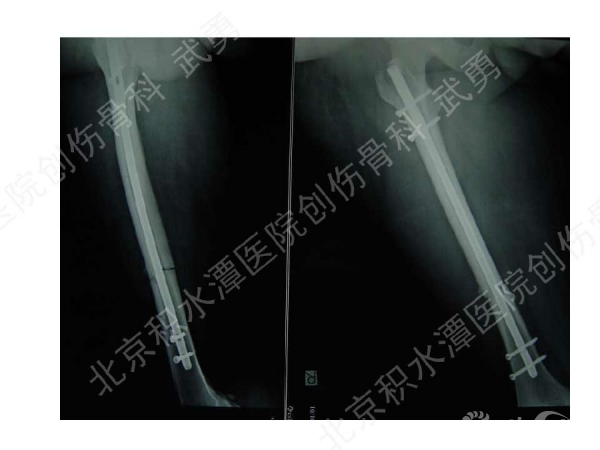

髓内钉骨不连的类型:增生型、萎缩型

病例分析:

有关畸形愈合:

主要发生在干骺端, 髓腔增宽,无法控制稳定(成角)

解决办法:阻挡钉技术(Poller screw)等